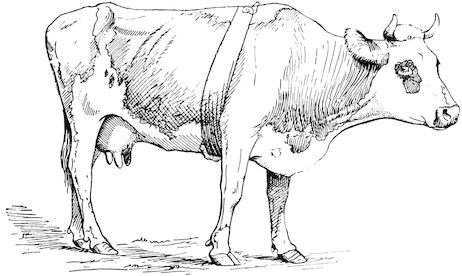

Fig. 3.—Pig suffering from osseous cachexia (fourth stage).

Such shocks would be of no importance to a healthy animal, but to one suffering from osseous cachexia, any violence, or even the slightest muscular effort may be followed by fracture of the gravest character, involving even the vertebral column. In cows the pelvis, femur, and tibia are most frequently injured.

In horses, particularly in riding horses, fractures are commonest in the region of the forearm, cannon bone, and anterior phalanges. So extremely fragile are the bones at this stage that the horse represented herewith broke twelve ribs at one time by simply falling on its side. It is interesting to note that such fractures are never accompanied by any extensive bleeding. They have little tendency to repair, no real callus formation occurs, and on post-mortem examination one often finds the ends unconnected by temporary callus, worn, and rounded by reciprocal friction.

At this stage but under other circumstances, the animals show great reluctance to rise, remaining down for twelve to twenty-four hours without shifting their position. If forced to get up, they stand as though fixed in one position, the respiration and circulation become rapid, and they soon grow tired and fall.

114. The fourth phase, or period of osteomalacia, i.e. softening of the bones, is also the last. It is rarely seen in large animals like horses and oxen, because accidents so often accompany the preceding stages and necessitate slaughter; but it is common in goats and pigs.

In this phase the bones become elastic, soft and depressible, yielding to the pressure of the operator’s fingers.

Fig. 4.—Deformity of the face in the horse shown in Fig. 2.

The flat bones are particularly liable to this change, which is common to domesticated animals. The bones of the head are the first to suffer; later those of the pelvis. The lower jaw becomes swollen, particularly about the centre of the branches which may attain three, four, or five times, their normal thickness.

The depression in the submaxillary space disappears. The upper jaw undergoes similar changes, becoming deformed and thickened until the cavities of the sinuses and the hollow appearance of the palate are lost, while the face is so changed that it cannot be recognised as that of a horse, goat, etc.

The molar teeth are almost buried, their tables alone being visible at the bottom of a depression, the edges of which rise above the neighbouring parts (pig).

Mastication is clearly impossible, the jaws appear paralysed, the muscles powerless, and only swallowing is possible, a fact which explains why life is only prolonged to this stage in animals which can be fed with a spoon or bottle (pigs and goats). The bones of the cranium, although greatly changed in texture, are always less deformed than those of the face.

The changes are such that it is often easy with a mere post-mortem knife to cut the head completely in two. Osseous tissue, properly so-called, has disappeared.

All the constituent tissues, with the exception of the skin and muscles, i.e., the bone, periosteum and aponeuroses, have the appearance and consistence on section of the fibro-lardaceous tissue seen in chronic inflammation.

Regarding the development of the disease in pigs, we may repeat what has just been said respecting the goat. Walking on the knees is often one of the first signs, fractures are somewhat rare, and the period of softening and deformity is always very noticeable.

14Course. The development of the disease is slow, lasting from one to three months as a rule, and is little influenced by hygienic conditions. Good milking cows, however, seem to be most frequently attacked, probably because of the great losses of nutritive material which occur through the milk. The calves borne by such animals are often rachitic. Oxen are less commonly attacked. Horses rarely suffer from the disease in France, but frequently in Tonquin. Pigs reared on very poor soil seldom escape attack.